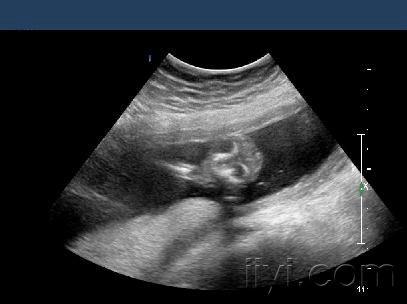

无脑儿胎儿畸形

无脑症是胚胎发育期间,出现颅骨缺陷,及脑部发育不全的罕见先天性

neural tube defects

无脑儿是常见的神经管畸形的一种.